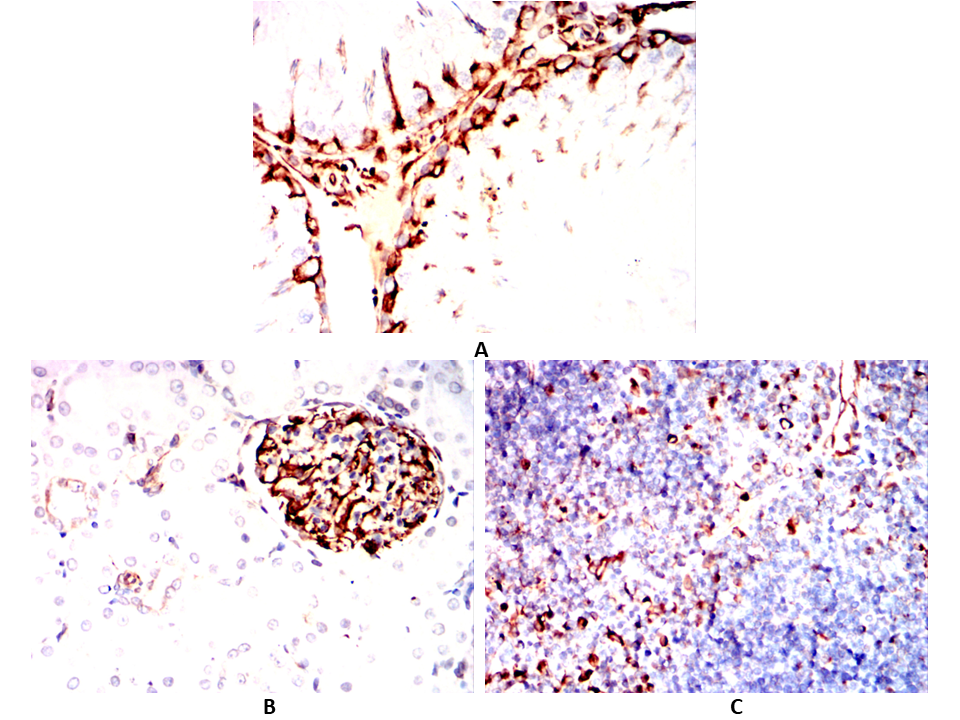

Immunohistochemical analysis of paraffin-embedded Mouse testicles(A)Mouse kidney(B)Mouse thymus(C) using CD276 mouse mAb with DAB staining.

-

Immunohistochemical analysis of paraffin-embedded Rat testicles(A)Rat kidney(B)Rat thymus(C) using CD276 mouse mAb with DAB staining.

Immunohistochemical analysis of paraffin-embedded Rabbit testicles(A)Rabbit kidney(B)Rabbit thymus(C) using CD276 mouse mAb with DAB staining.